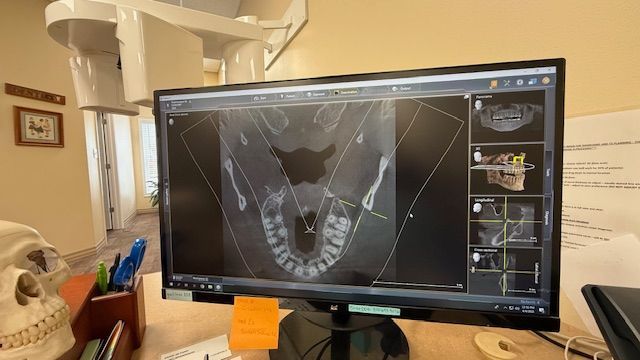

At our office, we’re proud to be one of the only dental practices in the region equipped with advanced Panoramic and Cone-Beam Computerized Tomography (CBCT) technology. Think of it like an MRI for your head, neck, and mouth—this powerful tool gives us detailed 3D images from multiple angles and “slices,” allowing us to detect issues, identify pathology, and deliver far more accurate diagnoses than traditional imaging. It’s just one of the ways we’re committed to providing the highest level of care.

The panoramic x-ray machine rotates around your head, capturing multiple images of your teeth, jawbone, sinuses, and surrounding soft tissues in one single scan. This creates a complete, 2D image that gives Dr. Westmoreland an enhanced view of your oral health. The entire process is quick and non-invasive, and you will only need to stand still for a few moments while the machine takes the image.

- Better Treatment Planning: The comprehensive images from a panoramic x-ray help us plan treatments with greater accuracy, whether you're undergoing a routine checkup, orthodontic evaluation, or preparing for dental surgery.